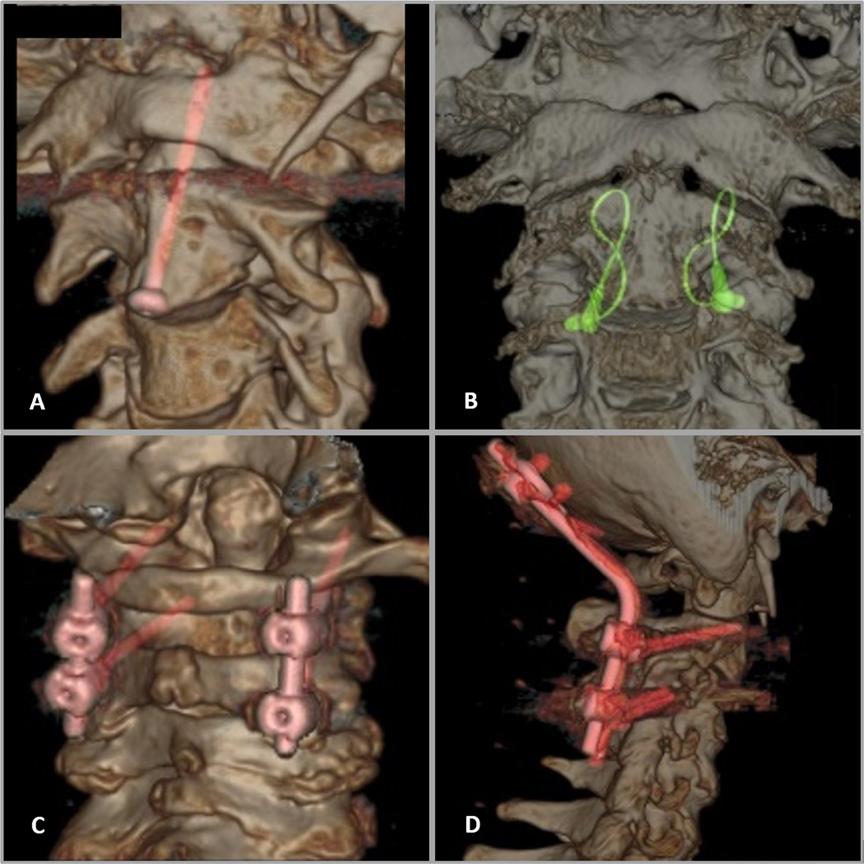

FIGUR 4: Noen av de hyppigst brukte operasjonsmetoder for å stabilisere densfraktur. Fremre osteosyntese med densskrue (A), cerclage wire med bengraft (B), bakre osteosyntese ad modum Harms (C), occipitocervical bakre osteosyntese (D). Samtykke innhentet fra pasientene.